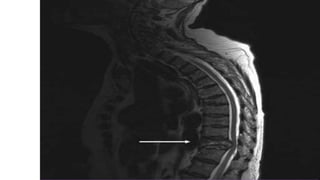

• Vertebral collapse- spinal cord compression

• Spinal cord compression from an extramedullary plasmacytoma/#(

5%) - Medical emergency

Cord compression Features S/o myelopathy Dexamethasone

Local Radiation

Surgical decompression